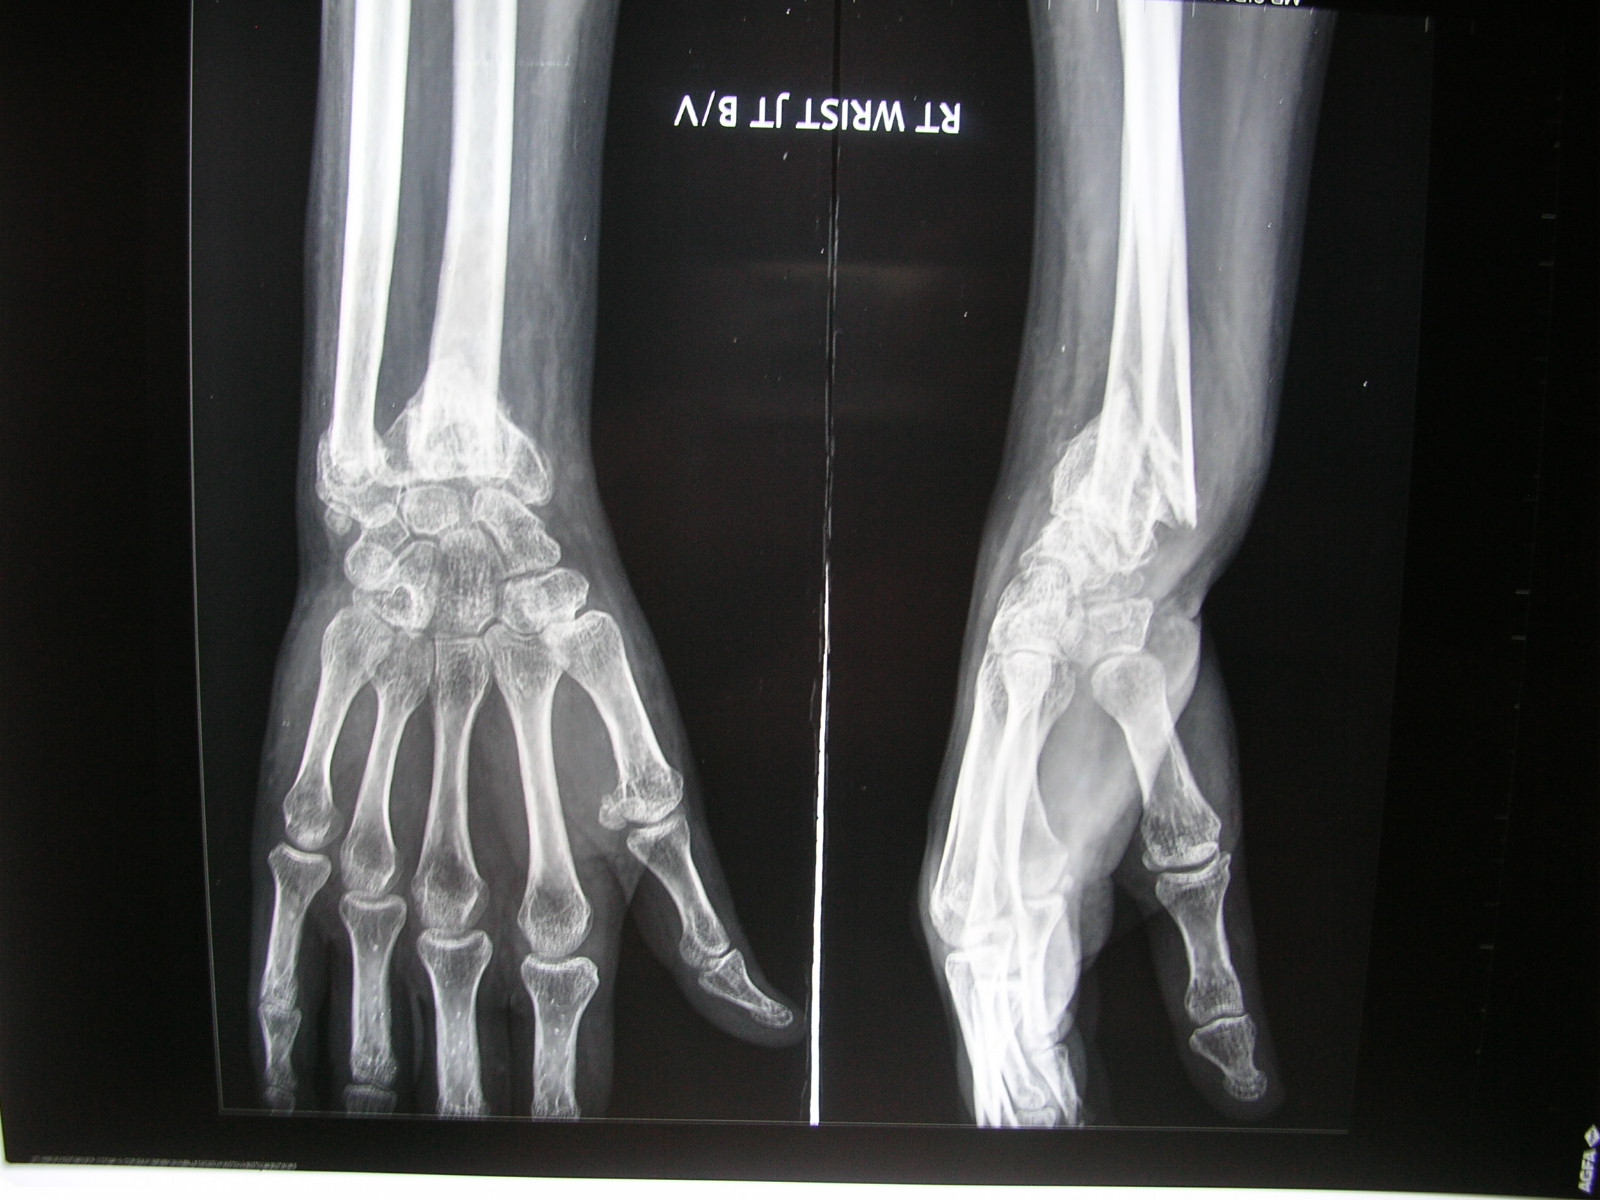

My Nurses Notes FRACTURE DISTAL END OF RT RADIUS AND STYLOID PROCESS Distal End Radius Ossification From the above mnemonic, we know that the time of appearance of proximal radius and ulna. — a classification into five ossification stages was applied to assess the epiphyseal development of distal. — for radius, the distal epiphysis started to appear from age group 1 in boys. — ossification of the wrist can be divided into two. Distal End Radius Ossification.

Xrays and Slides malunion of distal radiusulna fracture with Distal End Radius Ossification Proximal end, middle part and distal end of the right radial shaft. — a classification into five ossification stages was applied to assess the epiphyseal development of distal. — distal radius and ulna. — ossification of the wrist can be divided into two components: — length and transverse diameters for: — the distal ends of. Distal End Radius Ossification.